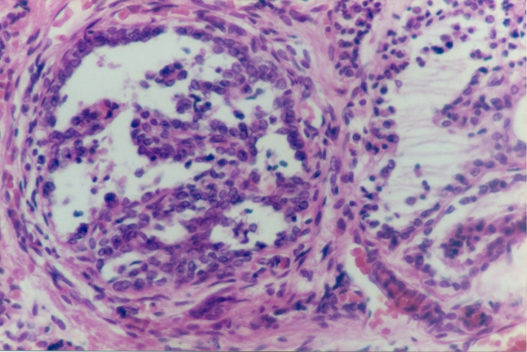

Carcinoma of the thyroid has been classified in this main histological types, papillary carcinoma, follicular carcinoma, medullary thyroid carcinoma and anaplastic carcinoma. Papillary carcinoma type. It is the more frequentlyseen in adults. We have find only one case of this type that presents acharacteristicnodule with papillary pattern (Figure 1). The aspect of nuclei of epithelial cells in no papillary areas are also atypical,looks more like those of the papillary area. Also there is a case with tall epithelial cells,that also have been related to papillary carcinoma (Figure 2).

Figure 1 Papillary nodule is seen. Appreciate that cells in no papillary areas, are different from cells of normal follicles.

Figure 2 In papillary carcinoma, a type has been describe with columnar cells.Picture showing that type of lesion.